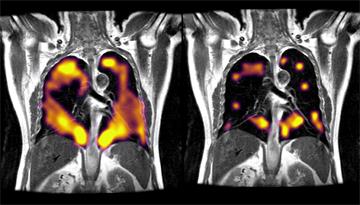

Xenon MRI imaging technology uses a novel approach that can detect functional changes of the lung that impact its ability to properly handle the exchange of gases during inhalation and exhalation. The upcoming research builds upon the pioneering work conducted at OUH showing that hyperpolarised xenon MRI can detect underlying damage that is not detectable by traditional lung imaging, such as CT scans.

The research builds upon the pioneering work conducted at OUH showing that hyperpolarised xenon MRI can detect areas of possible lung damage in patients with long COVID.

The EXPLAIN study is using hyperpolarised xenon MRI scans to investigate possible lung damage in long COVID patients who have not been hospitalised with COVID-19 but who continue to experience breathlessness.

The findings of an initial pilot study involving 36 people has identified abnormalities in the lungs of long COVID patients who had been experiencing breathlessness.

A polarisation device transforms the inert noble gas, xenon, into a hyperpolarised state using circularly polarised laser light. The hyperpolarised gas is inhaled by a patient to fill the space normally occupied by air in a single 10-second breath hold. The hyperpolarised gas then enhances the MRI signal, making regional lung function, including gas exchange, from the lungs to the blood visible in an MRI scan. The use of xenon MRI is non-invasive, and does not impart any radiation to the patient.